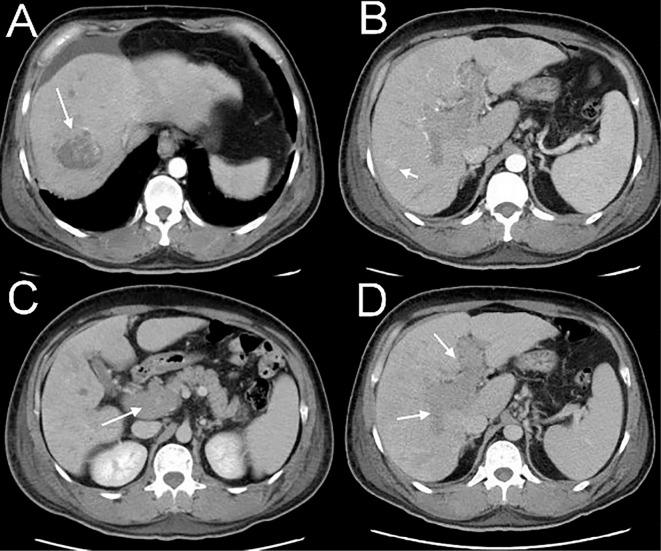

Dermatomyositis or polymyositis as a paraneoplastic syndrome of hepatocellular carcinoma (HCC) is an uncommon event. Few cases have been reported in the literature. We herein report the case of a 55-year-old man with chronic hepatitis B and alcoholism who presented with skin rash. Abdominal computed tomography revealed multiple hypervascular liver tumors consistent with HCC. He subsequently developed dysphagia with proximal limb weakness. Laboratory tests and electromyography demonstrated inflammatory myopathy. We therefore diagnosed the patient with HCC-induced dermatomyositis. Prednisolone and anti-viral therapy were administered; however, the patient died two months later due to the progression of the disease. We review the cases of HCC-induced dermatomyositis and polymyositis in the literature.